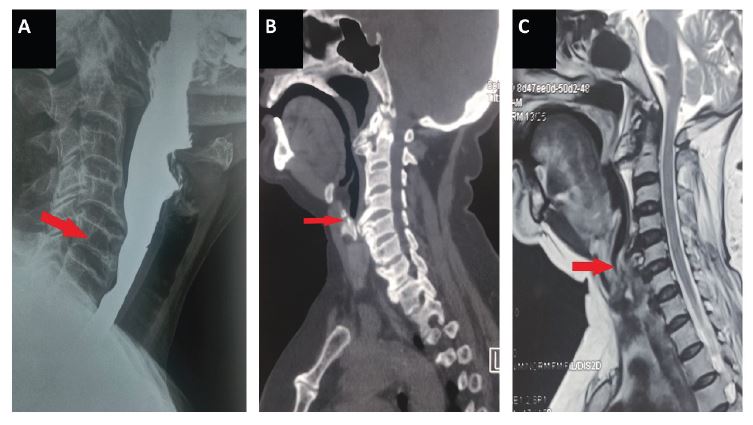

A 61 year old woman with no prior comorbidities presented to our department with symptoms of gradually progressive dysphagia for 2 year duration. Dysphagia was more for solids than liquids. According to the Atkinson Dysphagia severity grading scale, she had Grade 1 dysphagia [3]. She did not have a change in voice, nasal regurgitation, and difficulty in breathing. There was no history of vomiting, heartburnor chest pain. Her vitals were stable, and clinical examination was within normal limits. Barium swallow for the evaluation of dysphagia revealed osteophytes extending from C4-C5 and C5-C6 vertebral junction, causing smooth indentation over the posterior aspect of the esophagus. Further CT scan and MRI of the Neck was done, which showed degenerative changes in the cervical spine with a large anterior osteophyte indenting the esophagus. Upper GI Endoscopy revealed a smooth bulge just above the cricopharynx, with normal esophageal peristalsis. Spine surgeon consultation was obtained, and she was advised conservative management with monitoring. The nature of the disease was explained to the patient and kept in regular follow-up.

Figure 1: Anterior cervical osteophytes compressing the esophagus as demonstrated in barium swallow (A), CT scan (B), MRI C-Spine (C).